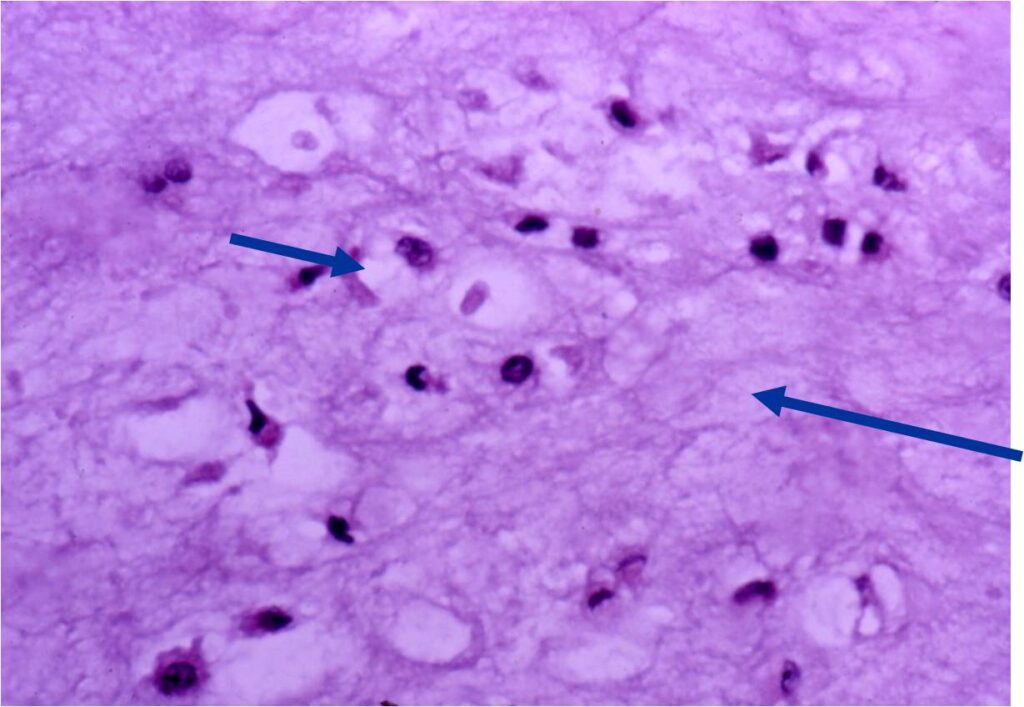

Pathology

- Rests of hyaline cartilage with a lobular growth pattern

- Cells are within lacunae

- Hypocellular with cells spaced apart separated by matrix

- Cells have small nuclei and are similar size and shape (no pleomorphism)

- No mitotic figures

- The matrix has a ground glass basophilic appearance

- The matrix contains glycosaminoglycans that attract fluid/water and gives it a bsophilic appearance and show as high signal intensity on T2 weighted MRI

- The collagen of the matrix is organized in a manner such that the refractile index under a microscope gives a ground glass appearance to the matrix. One can not visualize the actual collagen fibers.

- Hyaline cartilage often with myxoid areas

- Variable amorphous calcification and enchondral ossification

Microscopic Pathology

- Enchondromas are well defined lesions with cartilage arranged in lobules that are separated by fibrovascular septa

- Enchondral ossification may occur around periphery of lobules and when calcified appear as “Rings and Arcs” on X-rays

- Cells are in lacunae and have small dark nuclei

- Low cell count, cells appear bland with few chondrocytes and are similar size and shape

- Although some enchondromas may have areas that are hypercellular and may have two or three cells within a lacunae

- No entrapment or destruction of trabeculae

- There should be no myxoid change in long bone lesions (there is occasional myxoid change in enchondromas of the digits)

- Presence of myxoid change is sign of malignancy

Microscopic Pathology

- Hypercellular with large number of binucleated chondrocytes

- Higher degree of cellularity and atypia compared to isolated enchondroma

- Diagnosis of benign cartilage from a chondrosarcoma in setting of enchondromatosis is very difficult. Necrosis, myxoid change and radiographic studies demonstrating cortical destruction or a soft tissue mass are consistent with a chondrosarcoma